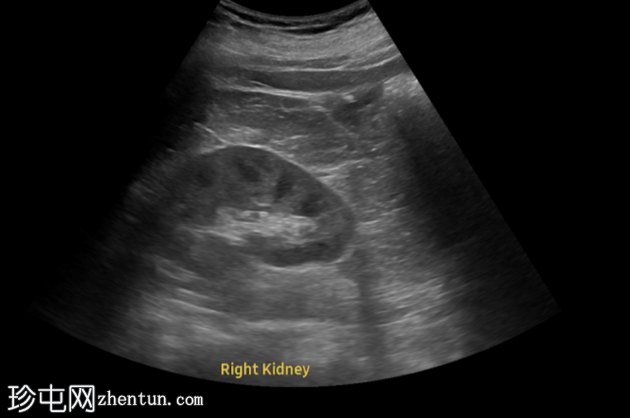

超声显示左侧轻度肾积水,由膀胱输尿管连接处一枚7毫米的远端输尿管结石阻塞所致,输尿管射流正常。

肾积水并非总是由输尿管结石引起。肾盂和肾盏扩张的程度与结石大小并不一定相关。

较小的结石有时可导致中度上游扩张,而较大的结石可能仅引起轻微的充盈感,这取决于患者的引流和水合状态。